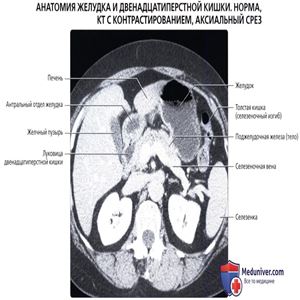

КТ с контрастированием: нормальное взаиморасположение желудка и прилегающих органов. Обратите внимание, что желудок может быть сдавлен увеличенной печенью или селезенкой.

Обратите внимание на малый сальник, содержащий жировую ткань, сосуды и лимфатические узлы желудка и печени.

Верхняя стенка желудка прилежит к поджелудочной железе, между ними расположен только малый сальник. Желчный пузырь прилежит к антральному отделу желудка и луковице двенадцатиперстной кишки. Большая кривизна желудка касается селезеночного изгиба толстой кишки.

Антральный отдел желудка прилежит к головке поджелудочной железы кзади и желчному пузырю сбоку.